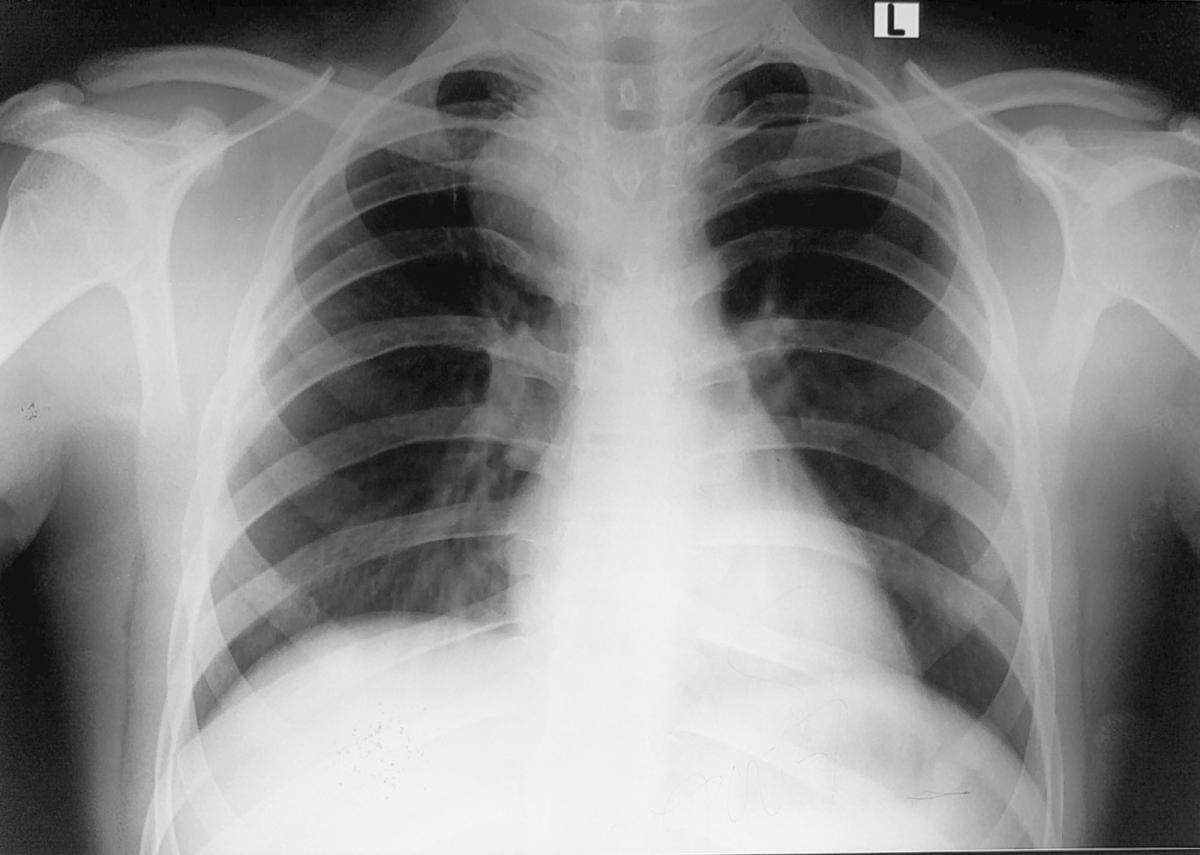

A 16-year-old boy presented with chest pain for the previous seven days that was more on the right side, gradual in onset, dull in character, intermittent, and radiating to the back. It was aggravated on exertion and was relieved with rest. The pain was associated with shortness of breath. The patient also complained of dysphagia, which was occasional and progressive. There was no history of cough or recent chest infection. General physical and systemic examinations were unremarkable. He had a low-grade fever with a hemoglobin of 13.5 g/dl, white cell count of 12.4/dL, and ESR of 52. Other routine lab investigations were within normal limits. His chest x-ray showed a right mediastinal round opacity on the right side of the carina. On his CECT scan Chest, the authors found a well-marginated nonenhancing thick fluid-attenuating lesion centered at the right paratracheal location in the middle and posterior mediastinum on the right side that was pressing on the esophagus and trachea.